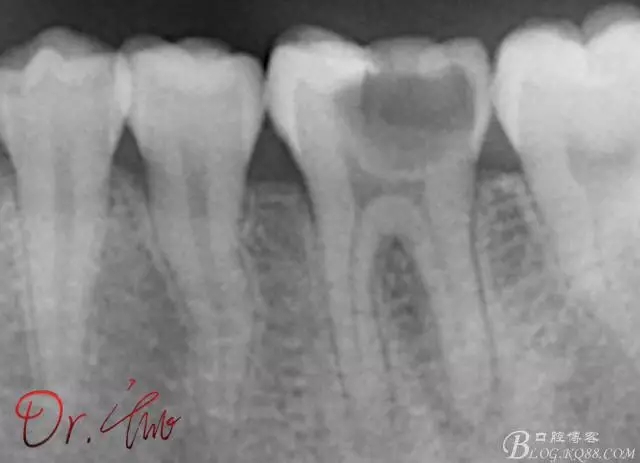

先來第一個病例

初診照

640.webp.jpg